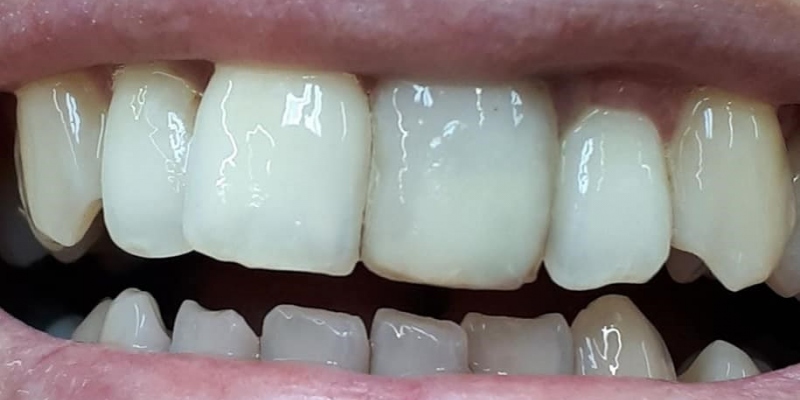

- SÓLO KORUNKY Kovokeramická korunka Bezkovová keramika Zirkón porcelán

Sólo korunky, nahradené implantátmi